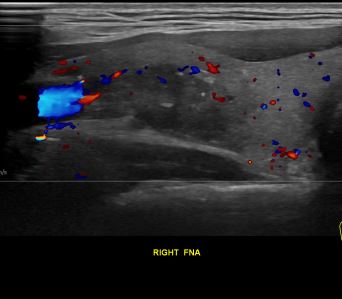

상기환자 외부건진이상소견 세침검사위해 내원하신 20대 중반 남성분으로

의심스러운 갑상선 우엽 결절 세포검사 진행후 갑상선암으로 진단되었습니다